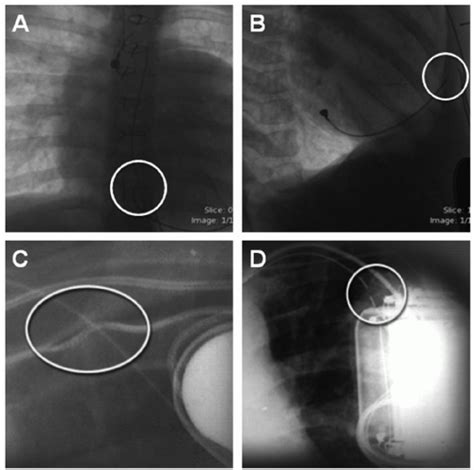

Each vertebral region has unique anatomical and functional features that result in specific injuries. U surgical timing is the only modifiable risk factor. Fracture of thoracic spinous process.

Treatment depends on the severity of the fracture and whether the patient has other associated injuries. In a pathological fracture sudden pain may follow a very trivial movement. Therefore diagnosis in the thoracic spine is more tentative and may have to be based on smaller, subtler abnormalities. Understanding how your spine works will help you. Collapsed vertebra, nec, thoracic region, init; They are also used to implications: Muscle relaxants for nonspecific low back pain: 806 fracture of vertebral column with spinal cord lesion. Struck by car • scenario: The break can cause one or more bones of the spine to collapse and may contribute to issues with supporting discs and nearby nerve roots. Eur spine j (2007) 16 (s.3): Most spinal fractures occur in the thoracic (midback) and lumbar spine (lower back) or at the connection of the two (thoracolumbar junction). The spinous process is long, relative to other regions, and is directed posteroinferiorly. A systematic review within the framework of the cochrane collaboration // spine. Fracture of thoracic vertebral arch. Midback anatomy explained with illustrations. • thoracic, thoracolumbar, and lumbosacral intervertebral disc disorders.